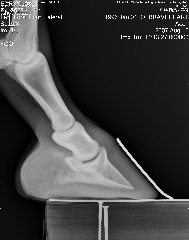

Posted on Friday, Aug 10, 2007 - 6:54 pm: We can trot on straight lines! Vet said he's at the limit from the coffin bone to the wall, that's not good, but he said he thought his angles looked ok. He thought that since the fetlock joints were off, he'd need more wall on the ;left front inside and more wall on the right front on the outside, then that should fix that. He said he'd like to see more sole, but he hooftested him and said his feet are rock hard so that should not be a worry for now. He's going to compare these to December's xrays and call. But based on what little he saw on the xrays and how he moved on the lunge, he said as long as I ride him in boots he should be just fine Here's a link to the xrays: https://s141.photobucket.com/albums/r59/wishes_album/xrays%20aug%2007/ Here are smaller versions: LF Lateral LF DP RF Lateral RF DP Edited to add that he was shocked that he could feel ribs when he asked Brave to move over But yes, he still is on a strict diet.

|

Posted on Friday, Aug 10, 2007 - 7:32 pm: Dr. O or anyone, Do his heels need to be lowered? I find it odd asking this question, but based on the xrays...Thanks! |

Posted on Friday, Aug 10, 2007 - 8:10 pm: Well, you can see from the laterals, his heels don't need to be higher. Are they back to the widest point of the frog? Breakover still looks too far forward to me if it's indicated by the white contrast line, but perhaps that's an illusion? |

Posted on Friday, Aug 10, 2007 - 8:43 pm: I don't think so... but they ARE better than they've been, I think, I just took these:Left front: Right front:

Posted on Friday, Aug 10, 2007 - 9:27 pm: and this from the vet that was extremely resistant to your going barefoot? to the point that you were afraid he'd DrOp you if you did?...hmmmmmmm.....i think you're heading in the right direction with his feet..breakover still needs to come back a tad, as well as the heel.. remmeber that the widest part of the foot should be at about the halfway point... his is farther back than that... that makes the breakover too far forward.. but they look tougher than ever and am so glad you've been given the ok to ride some... congrats and have fun!!! |